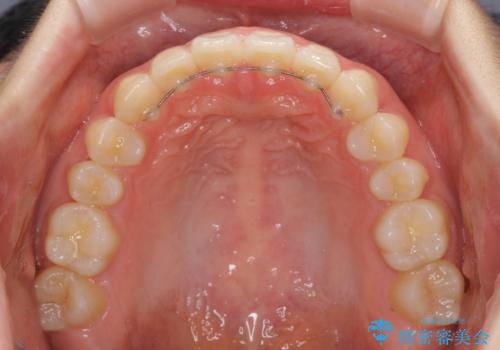

下顎の歯列が強く上顎に咬みこむことで隙間ができてしまうため、マウスピースの保定装置では後戻りのリスクが高くなってしまいます。

そのため、上下ともに前歯の裏側を細いワイヤーで固定し、その上から保定装置のマウスピースを使用していただくこととしました。